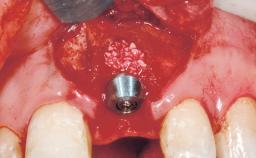

A 30-year-old female patient had lost tooth 21 and was referred to our clinic for consultation and treatment. Due to advanced apical infection, tooth 21 had been extracted two months earlier at another clinic and an acrylic-resin tooth had been bonded to the adjacent teeth. The patient desired implant treatment to avoid any damage to the adjacent natural teeth. While the patient had no history of any systemic disorder, she was a heavy smoker and exhibited medium to advanced periodontitis in the entire jaw. After the initial treatment to achieve a pocket probing depth of less than 4 mm and no bleeding on probing, a decrease in the height of the papillae mesial and distal to the extraction site and overall gingival recession were observed.

Type of Implants One-Piece|Reduced-Diameter

Bone Augmentation Horizontal|Staged

Augmentation Materials Autogenous chips|Membrane

Bone Volume Deficient horizontally, requiring prior grafting